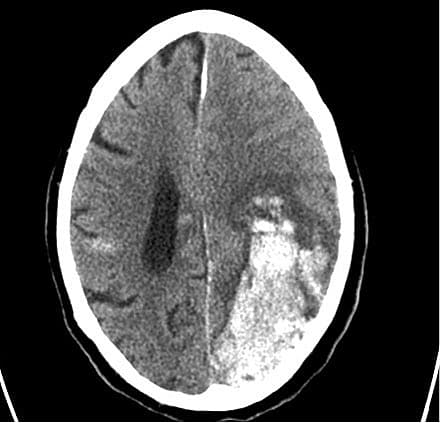

En 83-årig mand, der var i behandling med warfarin for kronisk atrieflimren, blev akut indlagt, da hans hustru fandt ham uden sprog og svær at komme i kontakt med. Han havde i hele sin mangeårige behandlingsperiode haft en stabil INR på 2,1-2,6. I 14 dage op til indlæggelsen havde han taget paracetamol 1 g × 4 og morfin 30 mg dagligt samt p.n. diclofenac. Ved indlæggelse var han vågen og havde en Glascow Coma Score (GCS) på 13, global afasi, højresidig kraftnedsættelse samt højresidig homonym hemianopsi. CT af cerebrum viste en stor parenkymblødning med midtlinjeforskydning. INR var over 10, og han blev behandlet med phytomenadion (K1-vitamin) samt koagulationsfaktor II, VII, IX og X (Octaplex). Efter 12 timers indlæggelse faldt GCS til 7. En fornyet CT af cerebrum viste progression af blødningen, gennembrud til ventrikelsystemet og begyndende inkarceration. Der var ingen kirurgiske behandlingsmuligheder, og efter otte døgn afgik patienten ved døden.

This is a case report of an 83-year-old man in warfarin treatment with stable international normalised ratio (INR) after aortic valve replacement and atrial fibrillation. Due to back pain he took paracetamol (acetaminophen) 4 g/day, morphine 30 mg/day and diclofenac as rescue medication for two weeks. After 14 days of treatment he was admitted to a hospital with acute neurological deficits, and a blood sample showed INR levels above 10. A CT-scan of the brain showed an intracerebral haemorrhage. The patient died eight days after admission. Mechanisms of the possible interaction between paracetamol and warfarin are discussed.